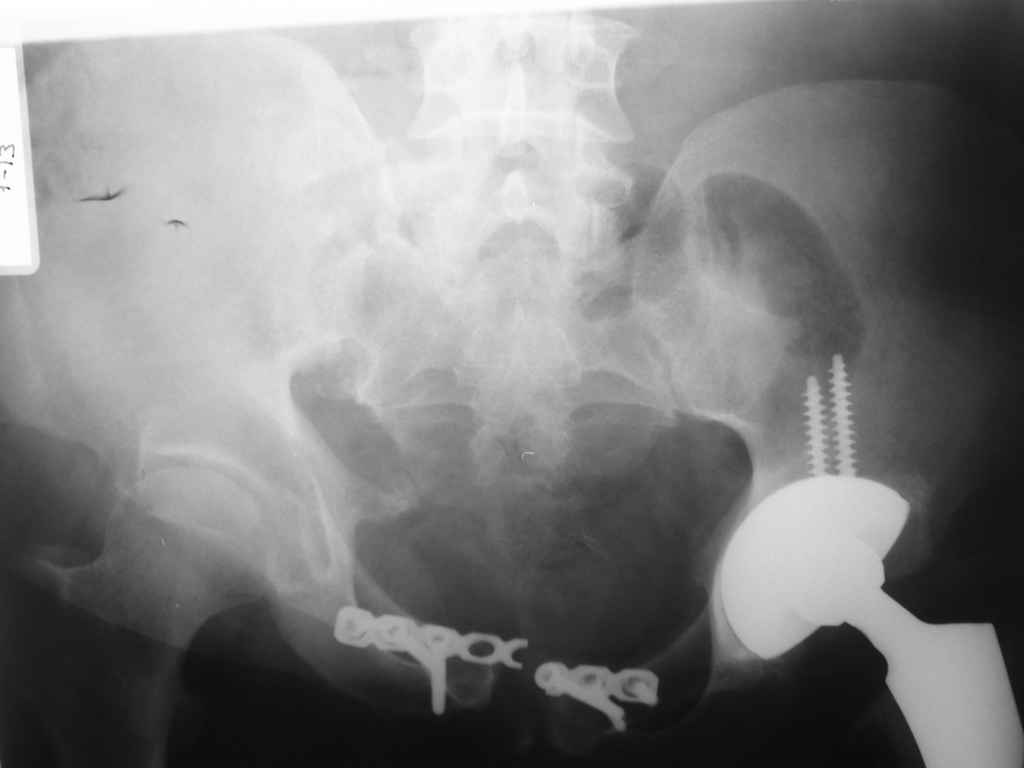

Это наблюдение 5-летней давности тогда кровопотеря составила 2,5 литра. В настоящий момент мы теряем не более 0,7-1,5 литров при одностороннем повреждении и около 2,5-3 литров тогда, когда речь идет о двусторонних повреждениях. Клинический пример.

прилагаю пример с такой же давностью травмы, репонировали аппаратом

Маленькая иллюстрация (около 5 лет после травмы). Результат плохой - укорочение, хромота, периодически боли в спине, но больной отказывается от операции, видимо, не так все трагично.